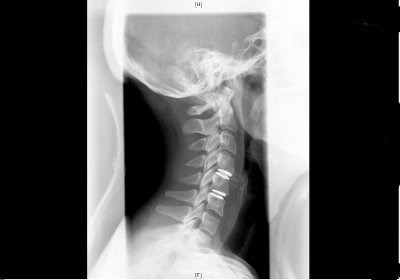

Columna cervical